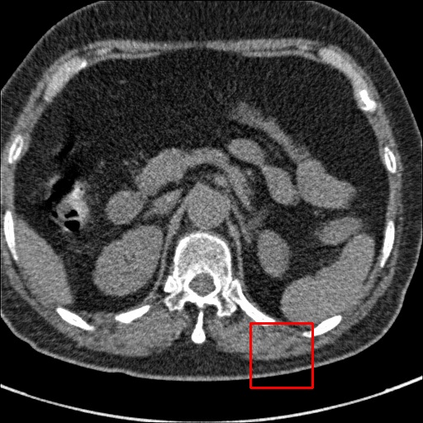

Low-Dose Computed Tomography (LDCT) technique, which reduces the radiation harm to human bodies, is now attracting increasing interest in the medical imaging field. As the image quality is degraded by low dose radiation, LDCT exams require specialized reconstruction methods or denoising algorithms. However, most of the recent effective methods overlook the inner-structure of the original projection data (sinogram) which limits their denoising ability. The inner-structure of the sinogram represents special characteristics of the data in the sinogram domain. By maintaining this structure while denoising, the noise can be obviously restrained. Therefore, we propose an LDCT denoising network namely Sinogram Inner-Structure Transformer (SIST) to reduce the noise by utilizing the inner-structure in the sinogram domain. Specifically, we study the CT imaging mechanism and statistical characteristics of sinogram to design the sinogram inner-structure loss including the global and local inner-structure for restoring high-quality CT images. Besides, we propose a sinogram transformer module to better extract sinogram features. The transformer architecture using a self-attention mechanism can exploit interrelations between projections of different view angles, which achieves an outstanding performance in sinogram denoising. Furthermore, in order to improve the performance in the image domain, we propose the image reconstruction module to complementarily denoise both in the sinogram and image domain.